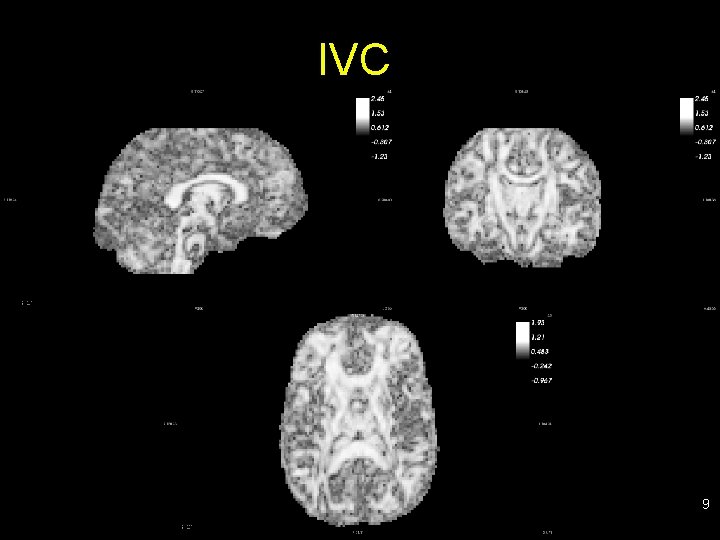

Examples of scalar maps • FA: fractional anisotropy (fiber density, axonal diameter, myelination in WM) • RA: relative anisotropy • VR: volume ratio • IVC: inter-voxel correlation (diffusion orientation agreement in neighbors) • ADC: apparent diffusion coefficient (magnitude of diffusion; low value organized tracts) • RD: radial diffusivity • AD: axial diffusivity • … 6

IVC 9